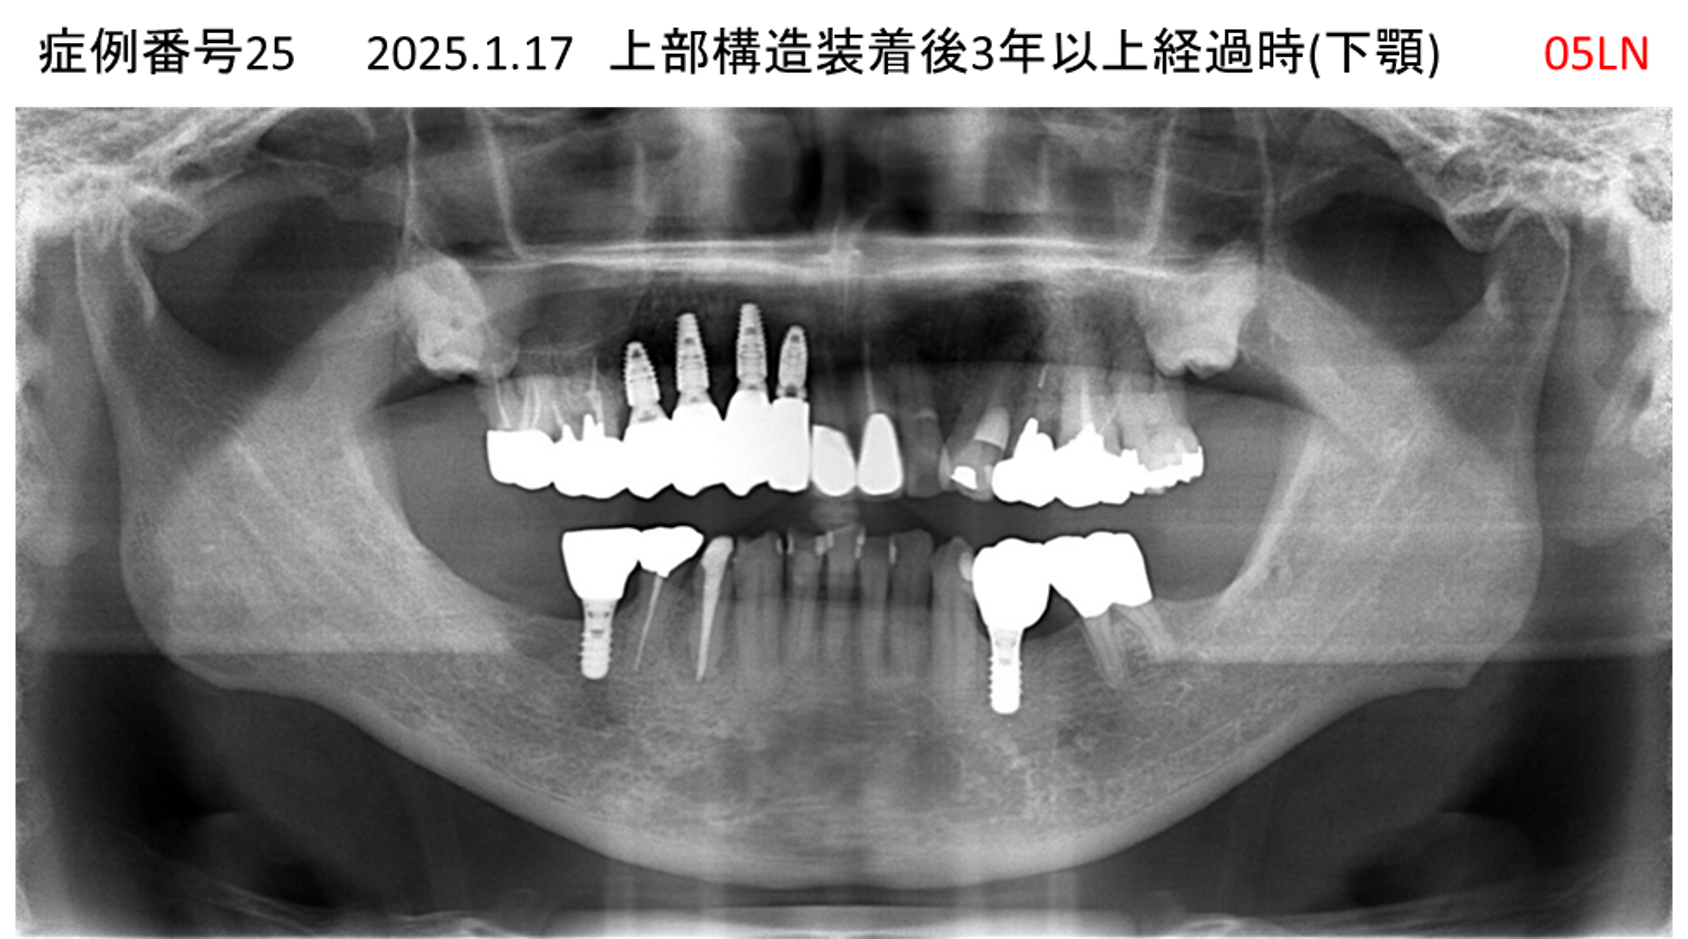

全く噛めない患者様のインプラント症例

| 治療名称 |

インプラントAGC |

| 治療費用 |

860万円+税 |

| 治療期間 |

12か月 |

| 患者さんの症状(主訴) |

全く噛めない、ごはんが後もに食べられるようになりたい、人前で口元を隠したくない |

| 治療内容 |

サイナスリフト、GBR、インプラント、AGC |

| 治療結果 |

しっかり噛めて踏ん張ることができる。食べ物をを選ばなくて済む、何でも食べられる、体重が増えた。見栄えがきれいすぎて自分じゃないみたい |

| 治療の注意点(リスク/副作用) |

インプラントが壊れたら再治療が必要 |